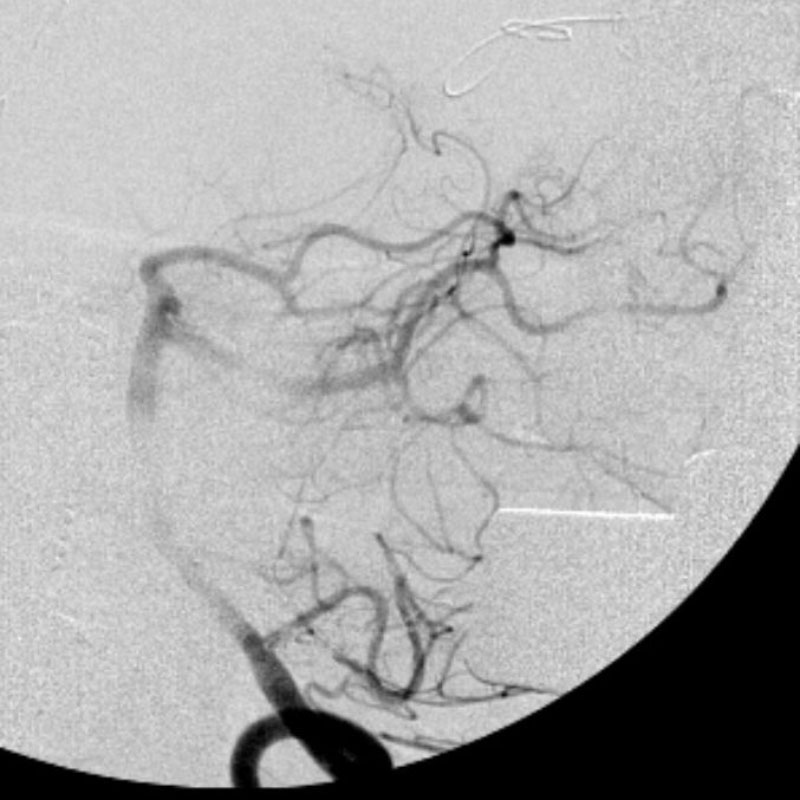

No.359 モニタリング

No.359 手術前

No.359 手術中

No.359 手術後

出血既往があり。2回の手術前血管内手術の後に、

Lateral transpeduncular approachにより再々出血予防を目的に

摘出手術を行う。完全摘出であることを確認した。

手術による合併症や後遺症なしで退院した。経過良好。